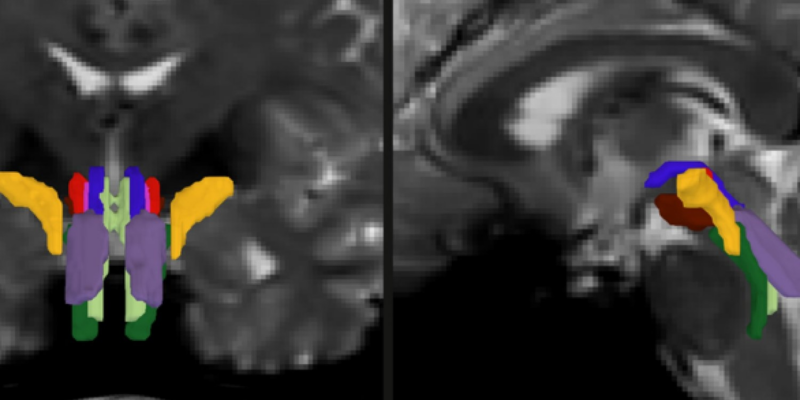

However, imaging the brainstem posed significant challenges due to its small size and its close proximity to pulsating fluids and moving organs. This is where the AI model steps in. It uses a convolutional neural network to analyze diffusion MRI scans, creating a probabilistic map of fiber pathways that descend into the brainstem. It then delves deeper to identify eight specific white matter bundles within the brainstem.

For BSBT to become a reliable tool, it had to be put through rigorous testing and validation. Olchanyi trained the system using 30 annotated diffusion MRI scans from the Human Connectome Project. The tool’s accuracy was then cross-verified by comparing its results with data from post-mortem brain dissections and ultra-high-resolution scans. BSBT’s reliability was confirmed when it successfully identified the same bundles in repeated scans of the same individuals.